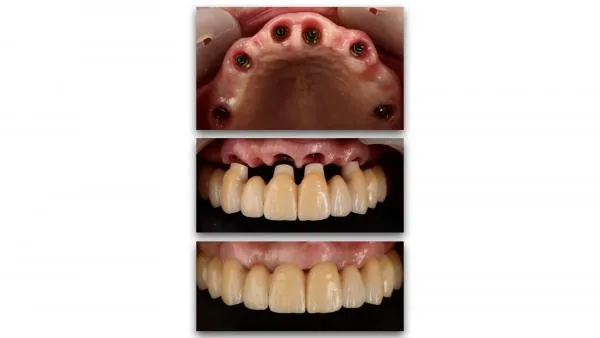

La démocratisation de nouvelles techniques comme le « Digital Smile Design », l’imagerie 3D, les outils de planification implantaire, les guides chirurgicaux stéréolithographiques, les empreintes optiques, la numérisation des modèles et la production par CFAO de piliers et de restaurations anatomiques optimisant nos profils d’émergence, contribuent à assurer la pérennité des restaurations implantaires à long terme.

De même l’amélioration de la prévisibilité des traitements, la mise en place des protocoles et la simplification des procédures cliniques et de laboratoire permettent aujourd’hui l’optimisation du résultat esthétique des restaurations implantaires, plus que jamais fidèles à la notion de « Biomimétisme ».

Le but de cette communication est de présenter une démarche thérapeutique reproductible, de la planification à la conception des restaurations implantaires unitaires et de grandes étendues, qui permet d’anticiper le résultat de nos traitements devenus de plus en plus complexes et de répondre aux principaux objectifs de l’implantologie moderne.